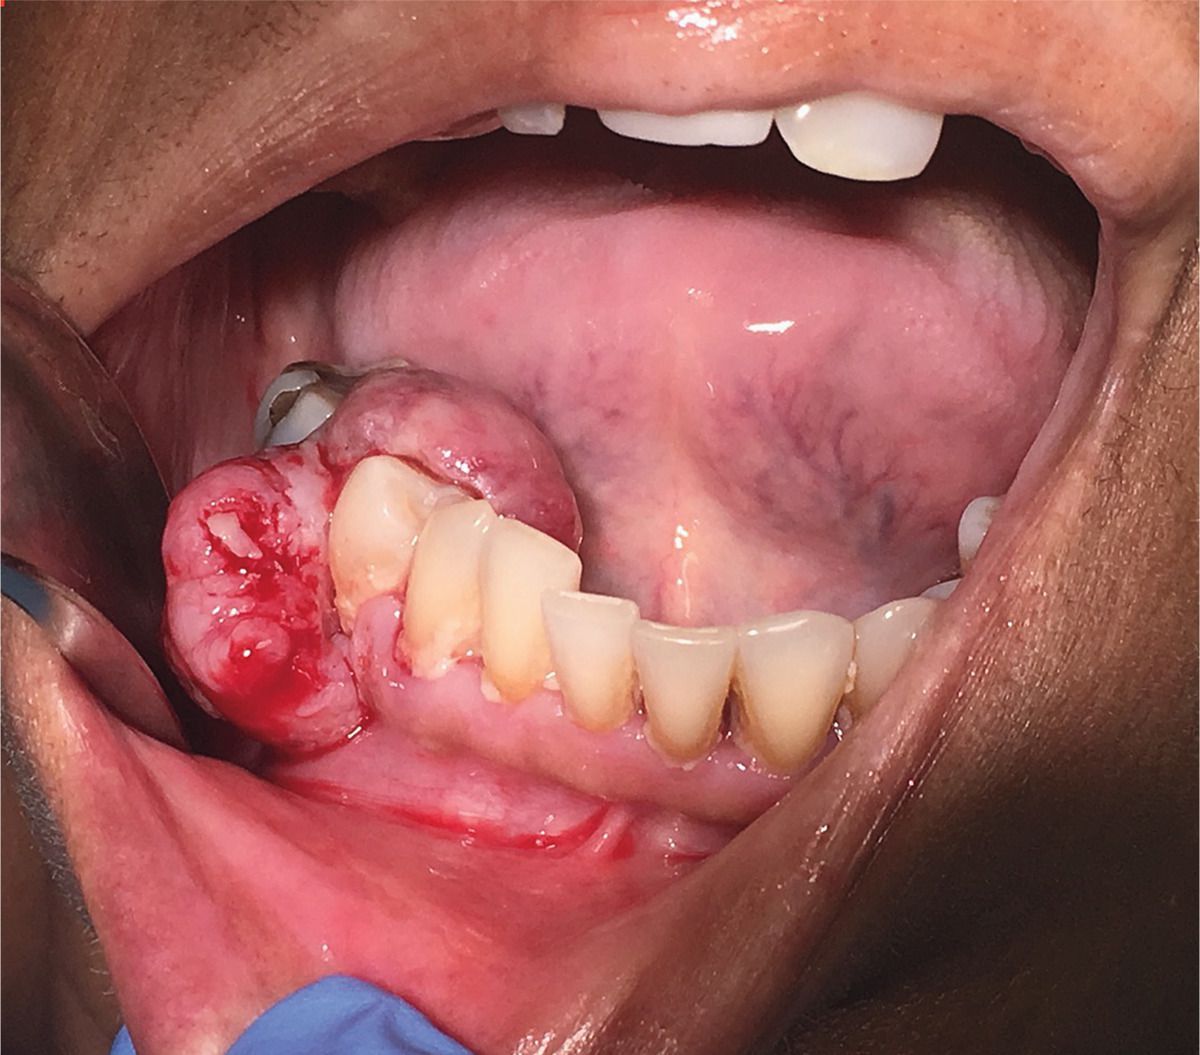

A 60-year-old woman presented to the oral surgery clinic with gingival swelling. She had a history of colorectal cancer, which had been diagnosed a year earlier, for which she had undergone surgery and received chemotherapy. She first noticed the mass after bleeding occurred while she was brushing her teeth. On examination, a large, nontender, pedunculated mass was seen extending from the buccal gingival border of the lower right second premolar to the lingual border. The surface was friable, and dental indentations on the occlusal aspect suggested chronicity. An excisional biopsy was performed, and histopathological analysis showed an infiltrating tumor, consistent with adenocarcinoma, probably of colorectal origin. At a follow-up visit 2 weeks later, further debulking of the tumor was performed. Positron-emission tomography showed multiple visceral metastases. The most common sites of metastasis of colorectal adenocarcinoma are the liver and lungs; metastatic lesions in the oral cavity are unusual. The patient was enrolled in a clinical trial of a chemotherapy regimen but was eventually lost to follow-up.